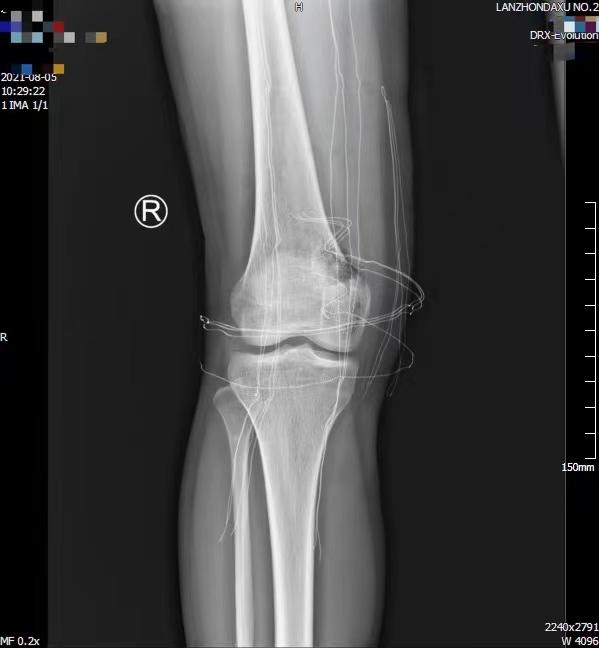

术后X线检查